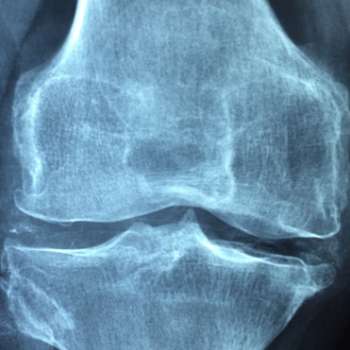

골다공증은 뼈의 밀도가 낮아지고 뼈 조직의 미세구조가 변형되어 뼈가 약해지는 질환입니다. 이로 인해 골절 위험이 증가하며, 특히 노인들에게 흔하게 발생합니다. 골다공증은 초기에는 특별한 증상이 없지만, 시간이 지남에 따라 다양한 증상이 나타날 수 있습니다. 여기에서는 골다공증의 주요 증상 10가지를 전문가적 관점에서 상세히 설명하겠습니다.

골다공증 증상 1. 뼈의 취약성 증가

골다공증의 가장 중요한 특징 중 하나는 뼈의 취약성이 크게 증가한다는 점입니다. 뼈가 약해져서 작은 충격이나 일상적인 활동에서도 쉽게 골절이 발생할 수 있습니다. 특히 척추, 고관절, 손목 등의 부위에서 골절이 자주 발생하며, 이러한 골절은 심각한 통증과 기능 장애를 초래할 수 있습니다. 예를 들어, 갑작스러운 낙상이나 가벼운 부딪힘으로 인해 손목 골절이나 고관절 골절이 발생할 수 있으며, 이는 환자의 일상생활에 큰 영향을 미칩니다.

골다공증 증상6. 관절 통증 및 강직

골다공증이 진행되면서 관절 주변의 뼈와 연골도 약해질 수 있습니다. 이는 관절 통증과 강직을 초래하며, 특히 아침에 일어날 때나 장시간 앉아 있다가 일어날 때 증상이 더 심해질 수 있습니다. 이러한 증상은 일상적인 움직임과 활동을 방해하고, 환자의 이동성을 제한합니다. 관절 통증은 특히 무릎, 엉덩이, 손목 등의 부위에서 흔히 발생하며, 이는 환자의 생활의 질을 저하시킬 수 있습니다.